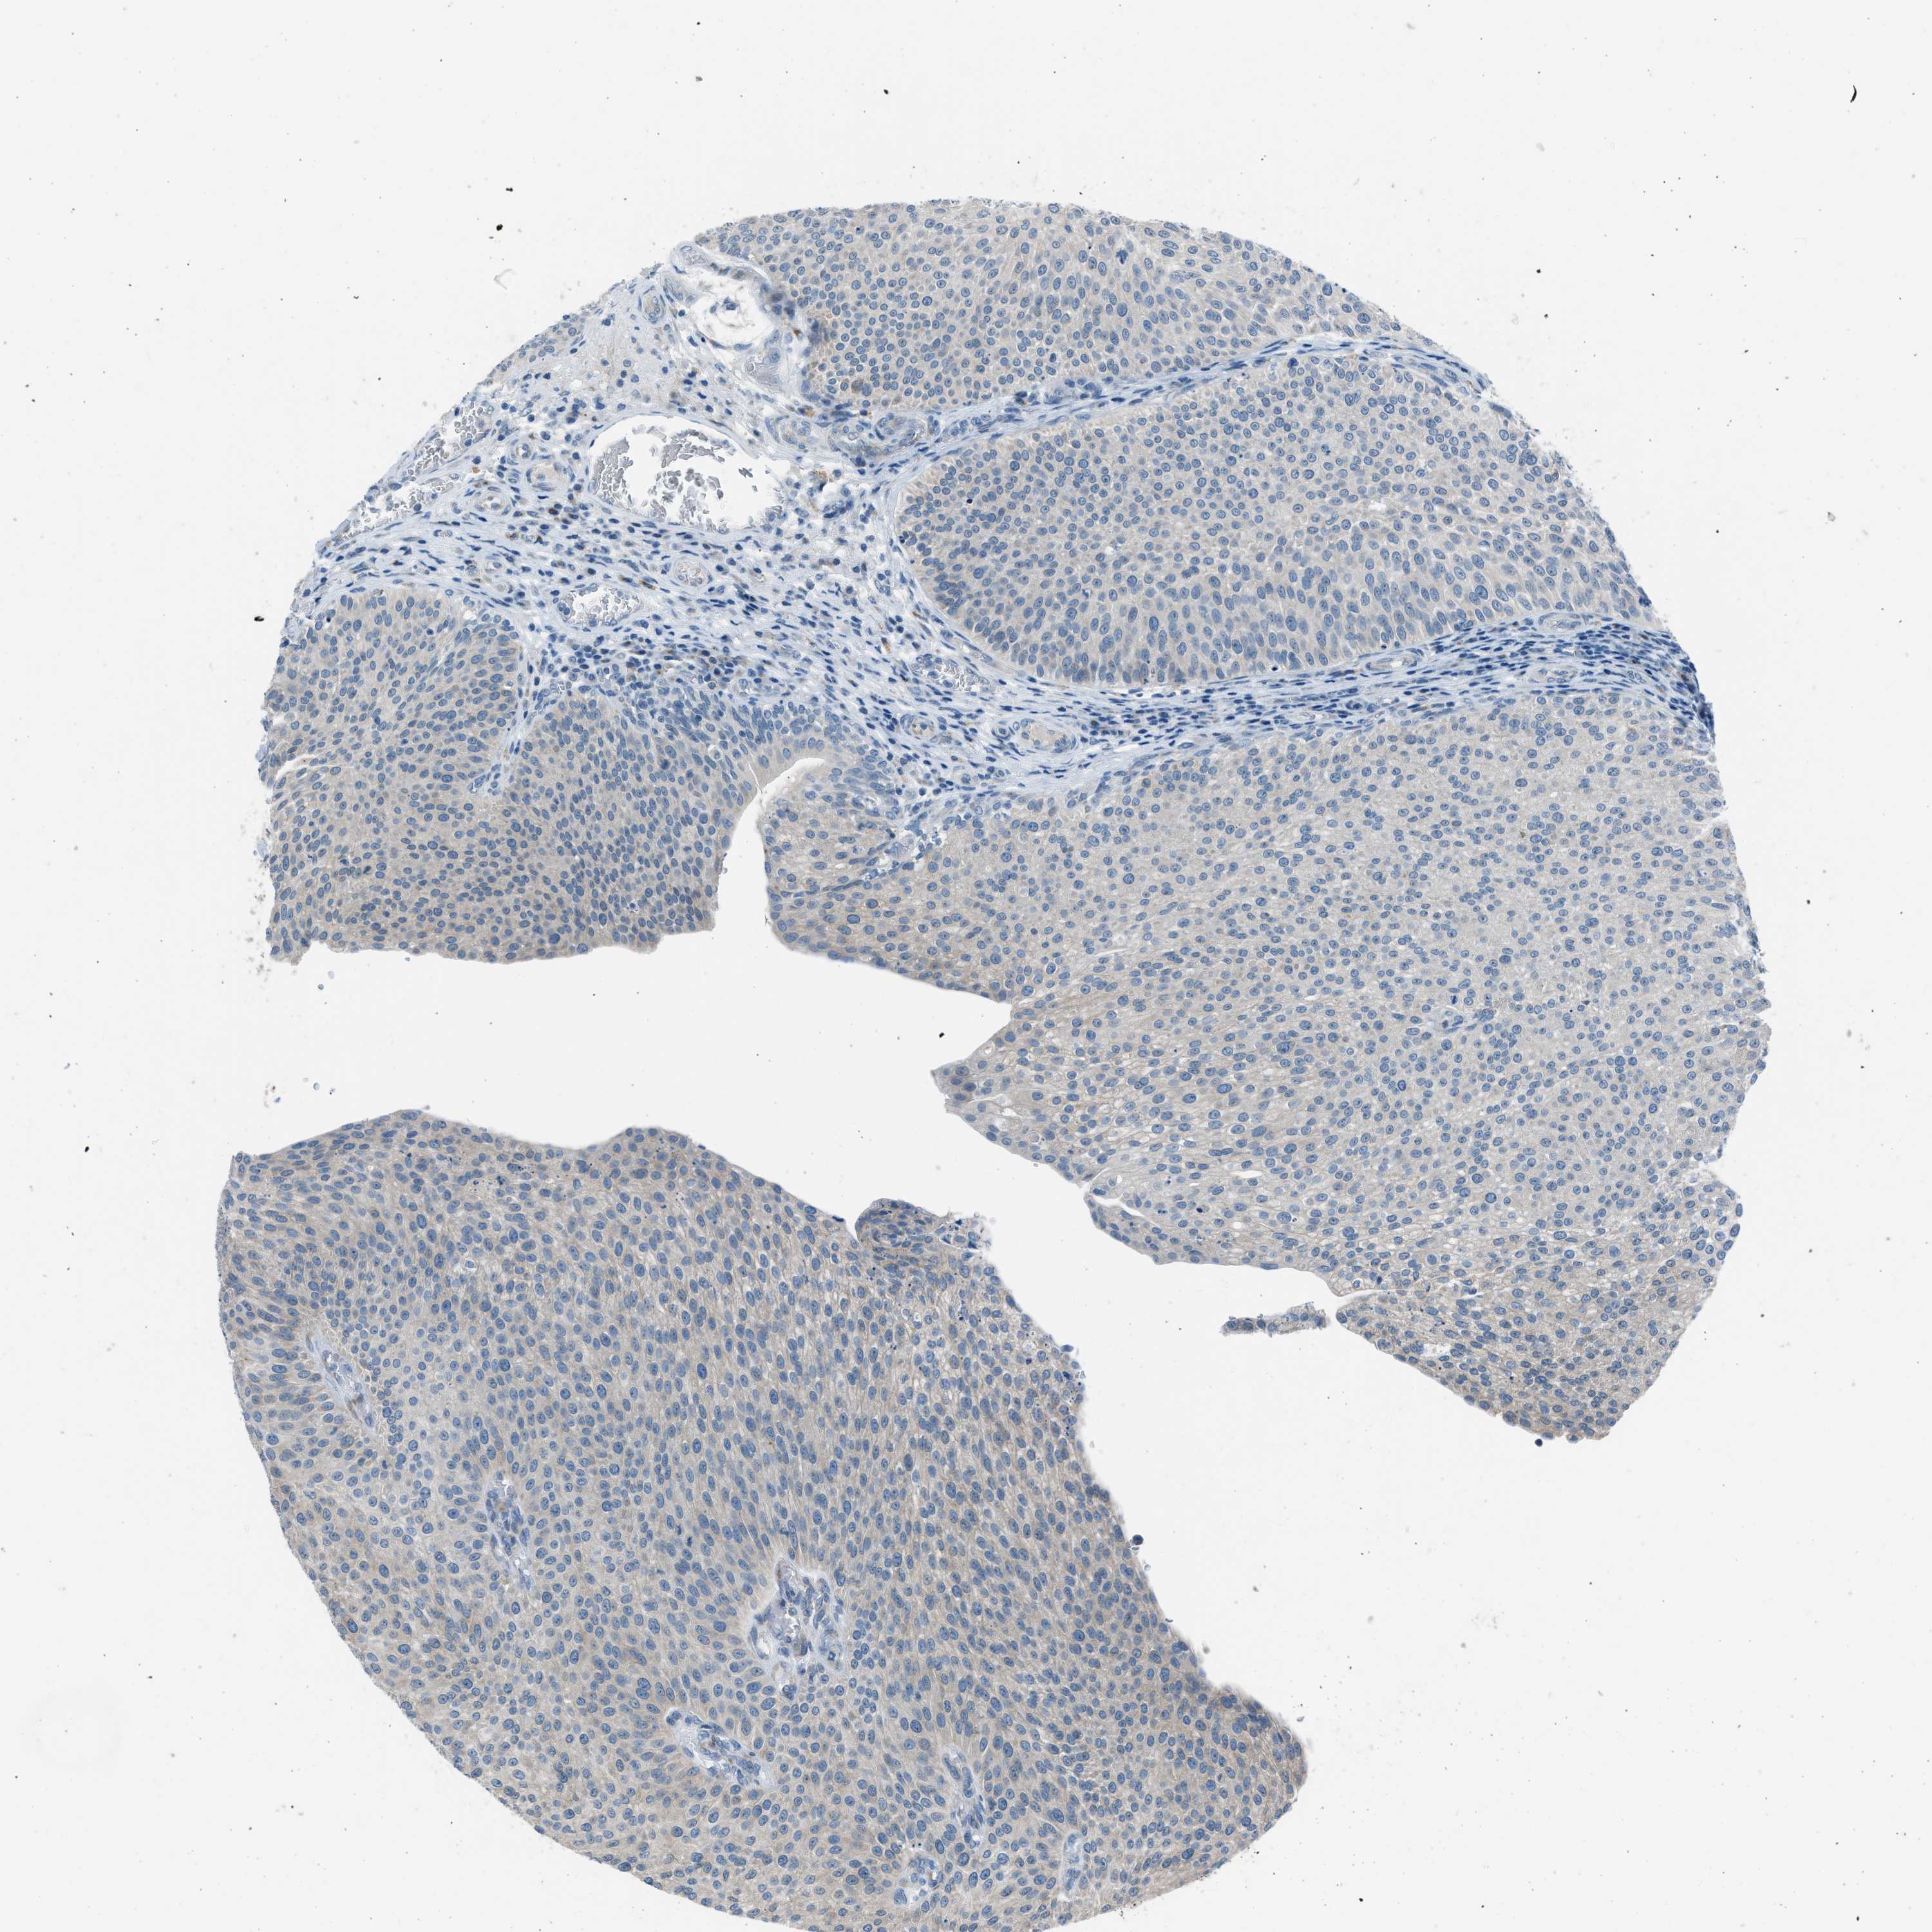

UROTHELIAL CANCER - Protein expressioni

A mouse-over function shows sample information and annotation data. Click on an image to view it in a full screen mode. Samples can be filtered based on level of antibody staining by selecting one or several of the following categories: high, medium, low and not detected. The assay and annotation is described here.

Note that samples used for immunohistochemistry by the Human Protein Atlas do not correspond to samples in the TCGA dataset.

Antibody stainingi

Antibody staining in the annotated cell types in the current human tissue is reported as not detected, low, medium, or high, based on conventional immunohistochemistry profiling in selected tissues. This score is based on the combination of the staining intensity and fraction of stained cells.

Each image is clickable and will lead to virtual microscopy that enables deeper exploration of all samples and also displays staining intensity scores, fraction scores and subcellular localization as well as patient and tissue information for each sample.

Antibody HPA016812

Staining

High

Medium

Low

Not detected

Intensity

Strong

Moderate

Weak

Negative

Quantity

>75%

75%-25%

<25%

None

Location

Nuclear

Cytoplasmic/membranous

Cytoplasmic/membranous,nuclear

Urothelial carcinoma, Low grade

Urothelial carcinoma, High grade